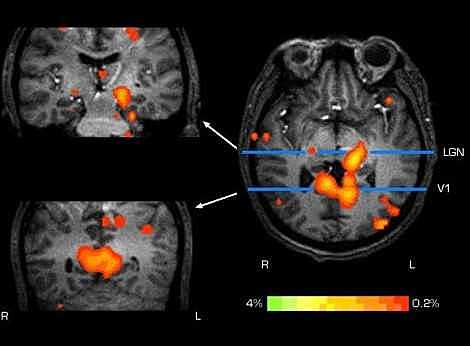

En 1971, apareció en escena Raymond V Damadian con un trabajo hoy clásico y que, como se refleja en los trabajos posteriores de Mallard y de Hollis,fue un aporte desafiante que estimuló el desarrollo posterior de la RM. Aquí Damadian propone: “Las medidas de resonancia spin-eco pueden ser usadas como un método para discriminar entre tumores malignos y tejido normal” El encontró diferencias en T1 y T2 entre seis muestras de tejidos normales y dos tumores sólidos del hígado y el riñon de la rata.

Después de 1971, influenciado por el trabajo de Damadian, Mallard exploró las diferencias de resonancia del protón entre tejidos cancerosos y normales encontrando resultados menos claros que los que reportó Damadian en 1971, explicando que gran parte de las diferencias en T1 eran dadas por la presencia de agua en estos tejidos

Peter Mansfield, físico inglés, descubrió el uso de gradientes de campo magnético producía señales que podrían ser analizadas para proveer la información espacial, incluyendo una descripción matemática de la transformación de una señal temporal a la representación espacial, introduciendo el concepto del espacio-K. Posteriormente siguió trabajando en la selección del corte y en 1976 propuso las secuencias EPI (eco-planar imaging), o como llenar el espacioK en forma rapidísima, en un solo disparo.

Peter Mansfield y Paul Lauterbur posteriormente siguieron contribuyendo al desarrollo de la RM, con gran número de artículos en la revista Physics in Medicine and Biology y en un artículo clásico, Mansfield y A.A. Maudsley en 1977 publicaron la primera imagen seccional de una región de la anatomía humana, un

dedo. P. Mansfield y P. Lauterbur fueron galardonados con el premio Nobel de Fisiología y Medicina de 2003